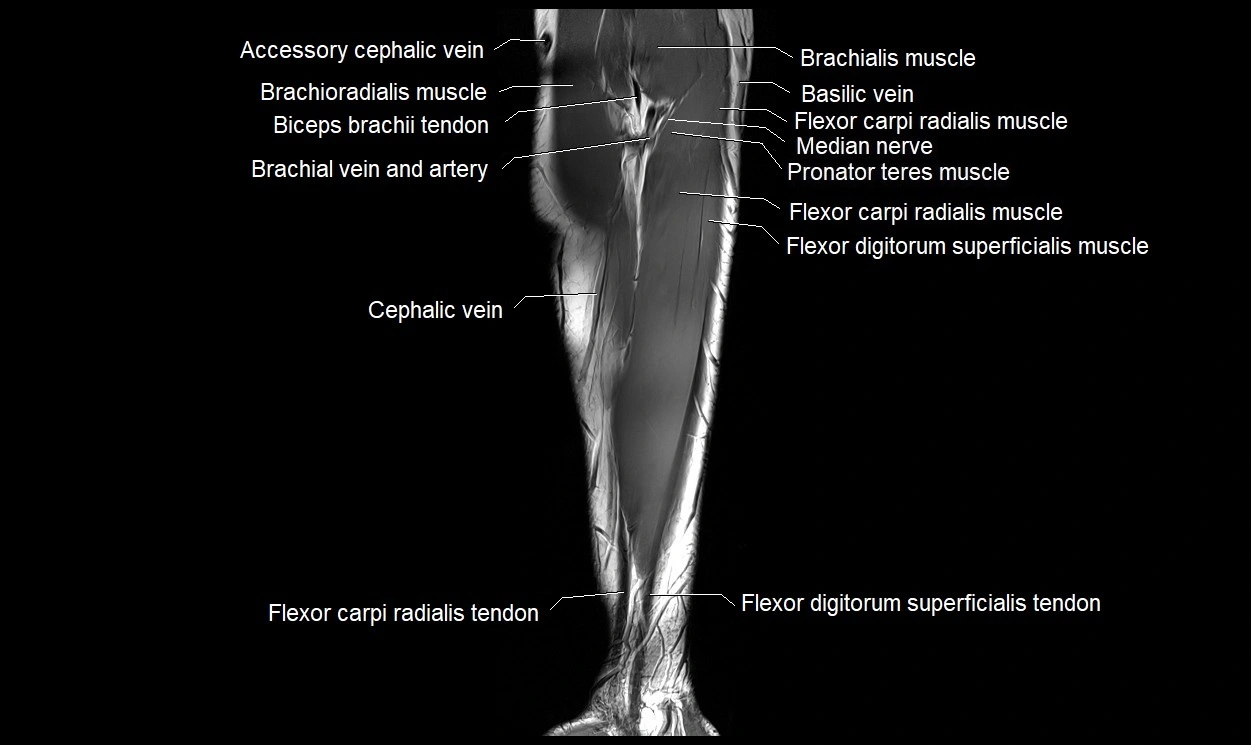

MRI images

image